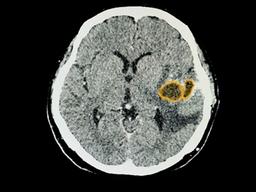

뇌 질환 의심될 땐?...저렴한 CT vs 비싼 MRI

낮아 뇌의 구조적인 변화를 자세히 살피는 데 한계가 있다. 또, 방사선

피폭

도 문제다. 통계적으로 뇌 CT는 2mSv의 방사선을 내뿜는다. 일반인의 연간 방사선 노출량 권고 기준치는 1mSv 이하다. 뇌 MRI 뇌 CT상으로 이상 소견이 발견되거나 명확하지 않은 부분이 있을 때는 뇌 MRI를 추가로 진행해 뇌 질환...